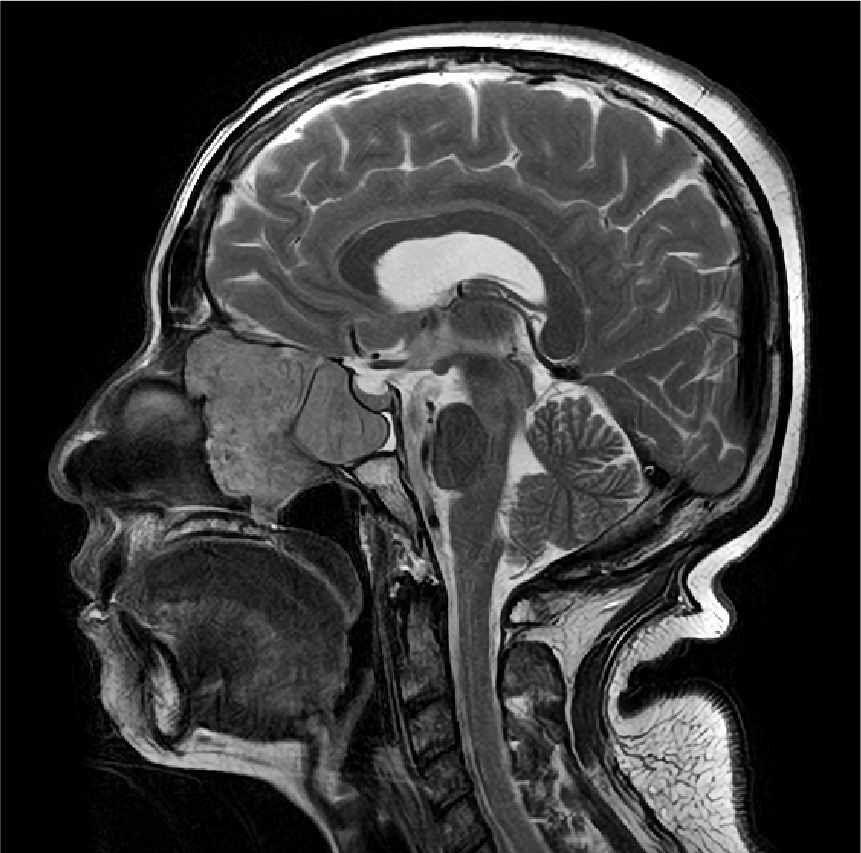

外視鏡と内視鏡を組み合わせて治療した腫瘍のMRI画像です。

髄膜腫:小脳、脳幹、聴神経などが圧迫されている

術前MRI

術後MRI